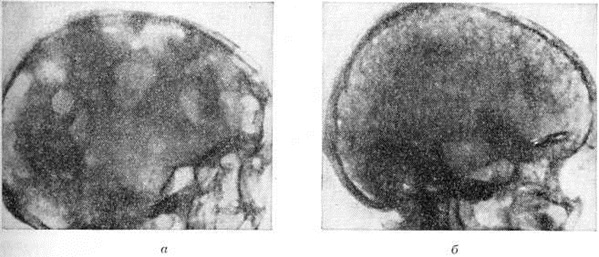

Множественно-очаговая форма встречается более чем в 70% случаев, рентгенологически характеризуется образованием множественных округлых дефектов диаметром до нескольких сантиметров. Изменения выявляются чаще всего в плоских костях (рисунок 9), реже — в длинных и коротких трубчатых. Каждый дефект чётко контурирован, реактивных изменений со стороны окружающей ткани при этом нет. В трубчатых костях корковое вещество изнутри истончается, костномозговая полость расширяется, на месте наиболее крупных узлов кость слегка вздувается и утолщается (рисунок 10, а). В ряде случаев может наблюдаться полное разрушение коркового вещества кости (рисунок 10, б) с распространением опухоли в мягкие ткани. Характерная картина выявляется при поражении костей черепа, в котором видны множественные, словно выбитые пробойником, дефекты кости (рисунок 11). В позвоночнике обнаруживается диффузное разрежение костной структуры, уплощение тел позвонков (бревиспондилия, «рыбьи позвонки»), искривление позвоночного столба. На фоне диффузного разрежения костного вещества тел позвонков заметна подчёркнутость дужек и отростков позвонков, что, как правило, отсутствует при метастатических поражениях позвоночника.

Рис. 11. | ||